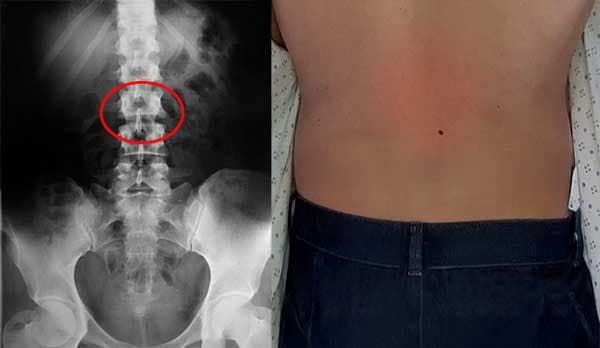

Kerusakan tulang belakang bagian bawah pada rontgen dan kenyataannya